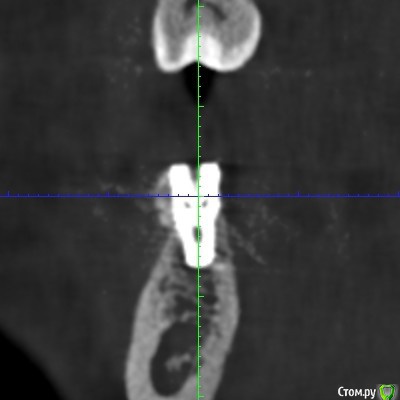

Irina_S Опубликовано 6 января, 2018 Поделиться Опубликовано 6 января, 2018 Здравствуйте, уважаемые спеицалисты! С наступившим вас Новым годом!!! В конце августа были установлены три имплантата Xive - 36, 46, 47. Одновременно с установкой выпиливалась кость и прикручивалась винтиками в те места, где по мнению хирурга её не хватало. В середине октября сквозь десну с язычной стороны стали просматриваться верхушки имплантатов 36 и 46. Во время периодических осмотров врач говорил, что всё в порядке.В декабре пришло время установки формирователей десны. Установивший имплантаты хирург стал работать в другой клинике. Он пригласил на осмотр, сказал, что надо будет добавить десну в области 36 и 46, взяв кусочки с нёба, а с самими имплантатами всё хорошо, можно одновременно с пластикой десны ставить формирователи и через 2-3 недели отправляться к ортопеду.Следуя логике сохранения гарантии на установку имплантатов, которую даёт не врач, а клиника, я пошла к другому хирургу в ту клинику, где устанавливались имплантаты. Он посмотрел на выступающие верзушки имплантатов, причём 36 успел к этому времени уже прорвать десну. Посмотрел КТ и сказал, что предварительно видит проблемы и помимо пластики десны может понадобиться переустановка имплантатов. Самый проблемный, по его мнению, 46, а 36 - под вопросом. Сказал, что окончательное решение можно будет принять только после разрезания десны, чтобы увидеть фактическую ситуацию. Причём переустановка - по гарантии, и она будет делаться сразу - выкручивается старый имплантат и ставится новый, тоньше (3,8мм вместо 4,5мм) и длиннее. Соответственно, в этом случае снова ждать 3-4 месяца, и только после этого ставить формирователи. Присутствовавший на консультации ортопед был полностью с ним согласен и сказал, что на имплантаты в таком состоянии, как он их видит на КТ, он коронки ставить не будет. Аргументировалось тем, что кости в принципе достаточно, но имплантаты надо было устанавливать глубже, а так, как сейчас, они протянут максимум 3-4 года, а потом расшатаются и выпадут. Клиника даёт гарантию 10 лет, поэтому они считают, что нужно хорошо установить изначально.На месяц раньше ставились имплантаты в верхнюю челюсть, с ними всё хорошо. Но, рассматривая проекции КТ, я вижу обширные тёмные области в районе всех имплантатов как дефект засветки при формировании КТ. В связи с чем вопрос: может ли картина на КТ с отсутствием видимой костной ткани происходить из-за самого оборудования, на котором делается КТ, и не совсем соответствовать действительности? Иначе, есть ли шанс, что при вскрытии десны окажется, что с расположением импллантатов всё в порядке (как и уверяет "сбежавший" их этой клиники хирург), а альтернативное мнение связано в некотором роде с желанием опозорить уволившегося сотрудника и удержать пациента у себя, ведь потом предстоит большая ортопедическая работа? И ещё один вопрос: чего мог категорически не принимать ортопед, говоря, что в подобных случаях он всегда отправляет к хирургу, если заведомо было известно, что недостающая десна в любом случае будет наращиваться?С имплантатом 47 ситуация, вроде бы, не такая критическая. Это на самом деле так? Ссылка на комментарий

колесников Опубликовано 6 января, 2018 Поделиться Опубликовано 6 января, 2018 С десной однозначно предстоит поработать. Импланты расположены несколько язычно,что может быть проблематично. Ссылка на комментарий

колесников Опубликовано 6 января, 2018 Поделиться Опубликовано 6 января, 2018 Сколько врачей,столько и клинических подходов. Я бы переустановил нижние импланты заменив ксайв на Штрауман тл, плюс увеличил объём мягких тканей по гребню.Это ,как говорится ,обойтись малой кровью с благоприятным прогнозом. Если оставлять этот ксайв,то только пластики десны не достаточно,придётся перекрывать их костным материалом с мембраной и позднее Увеличить объём мягких тканей. Все бы ничего,но меня смущает язычное положение платформ имплантов и их уровень относительно соседних зубов. Это лично моё мнение,оно может отличаться от мнений коллег. Ссылка на комментарий